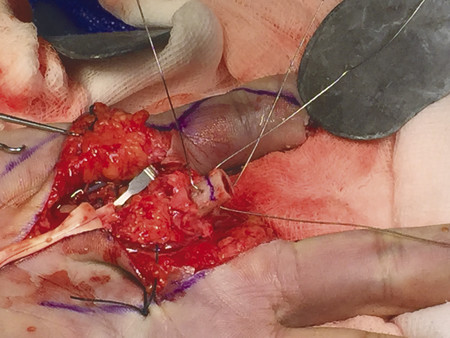

Fig. 12.12 Bone ends are shortened in preparation for osteosynthesis. Glove used to protect neurovascular bundles.

Fig. 12.13 Cross-clamping method to stabilize bone before shortening.